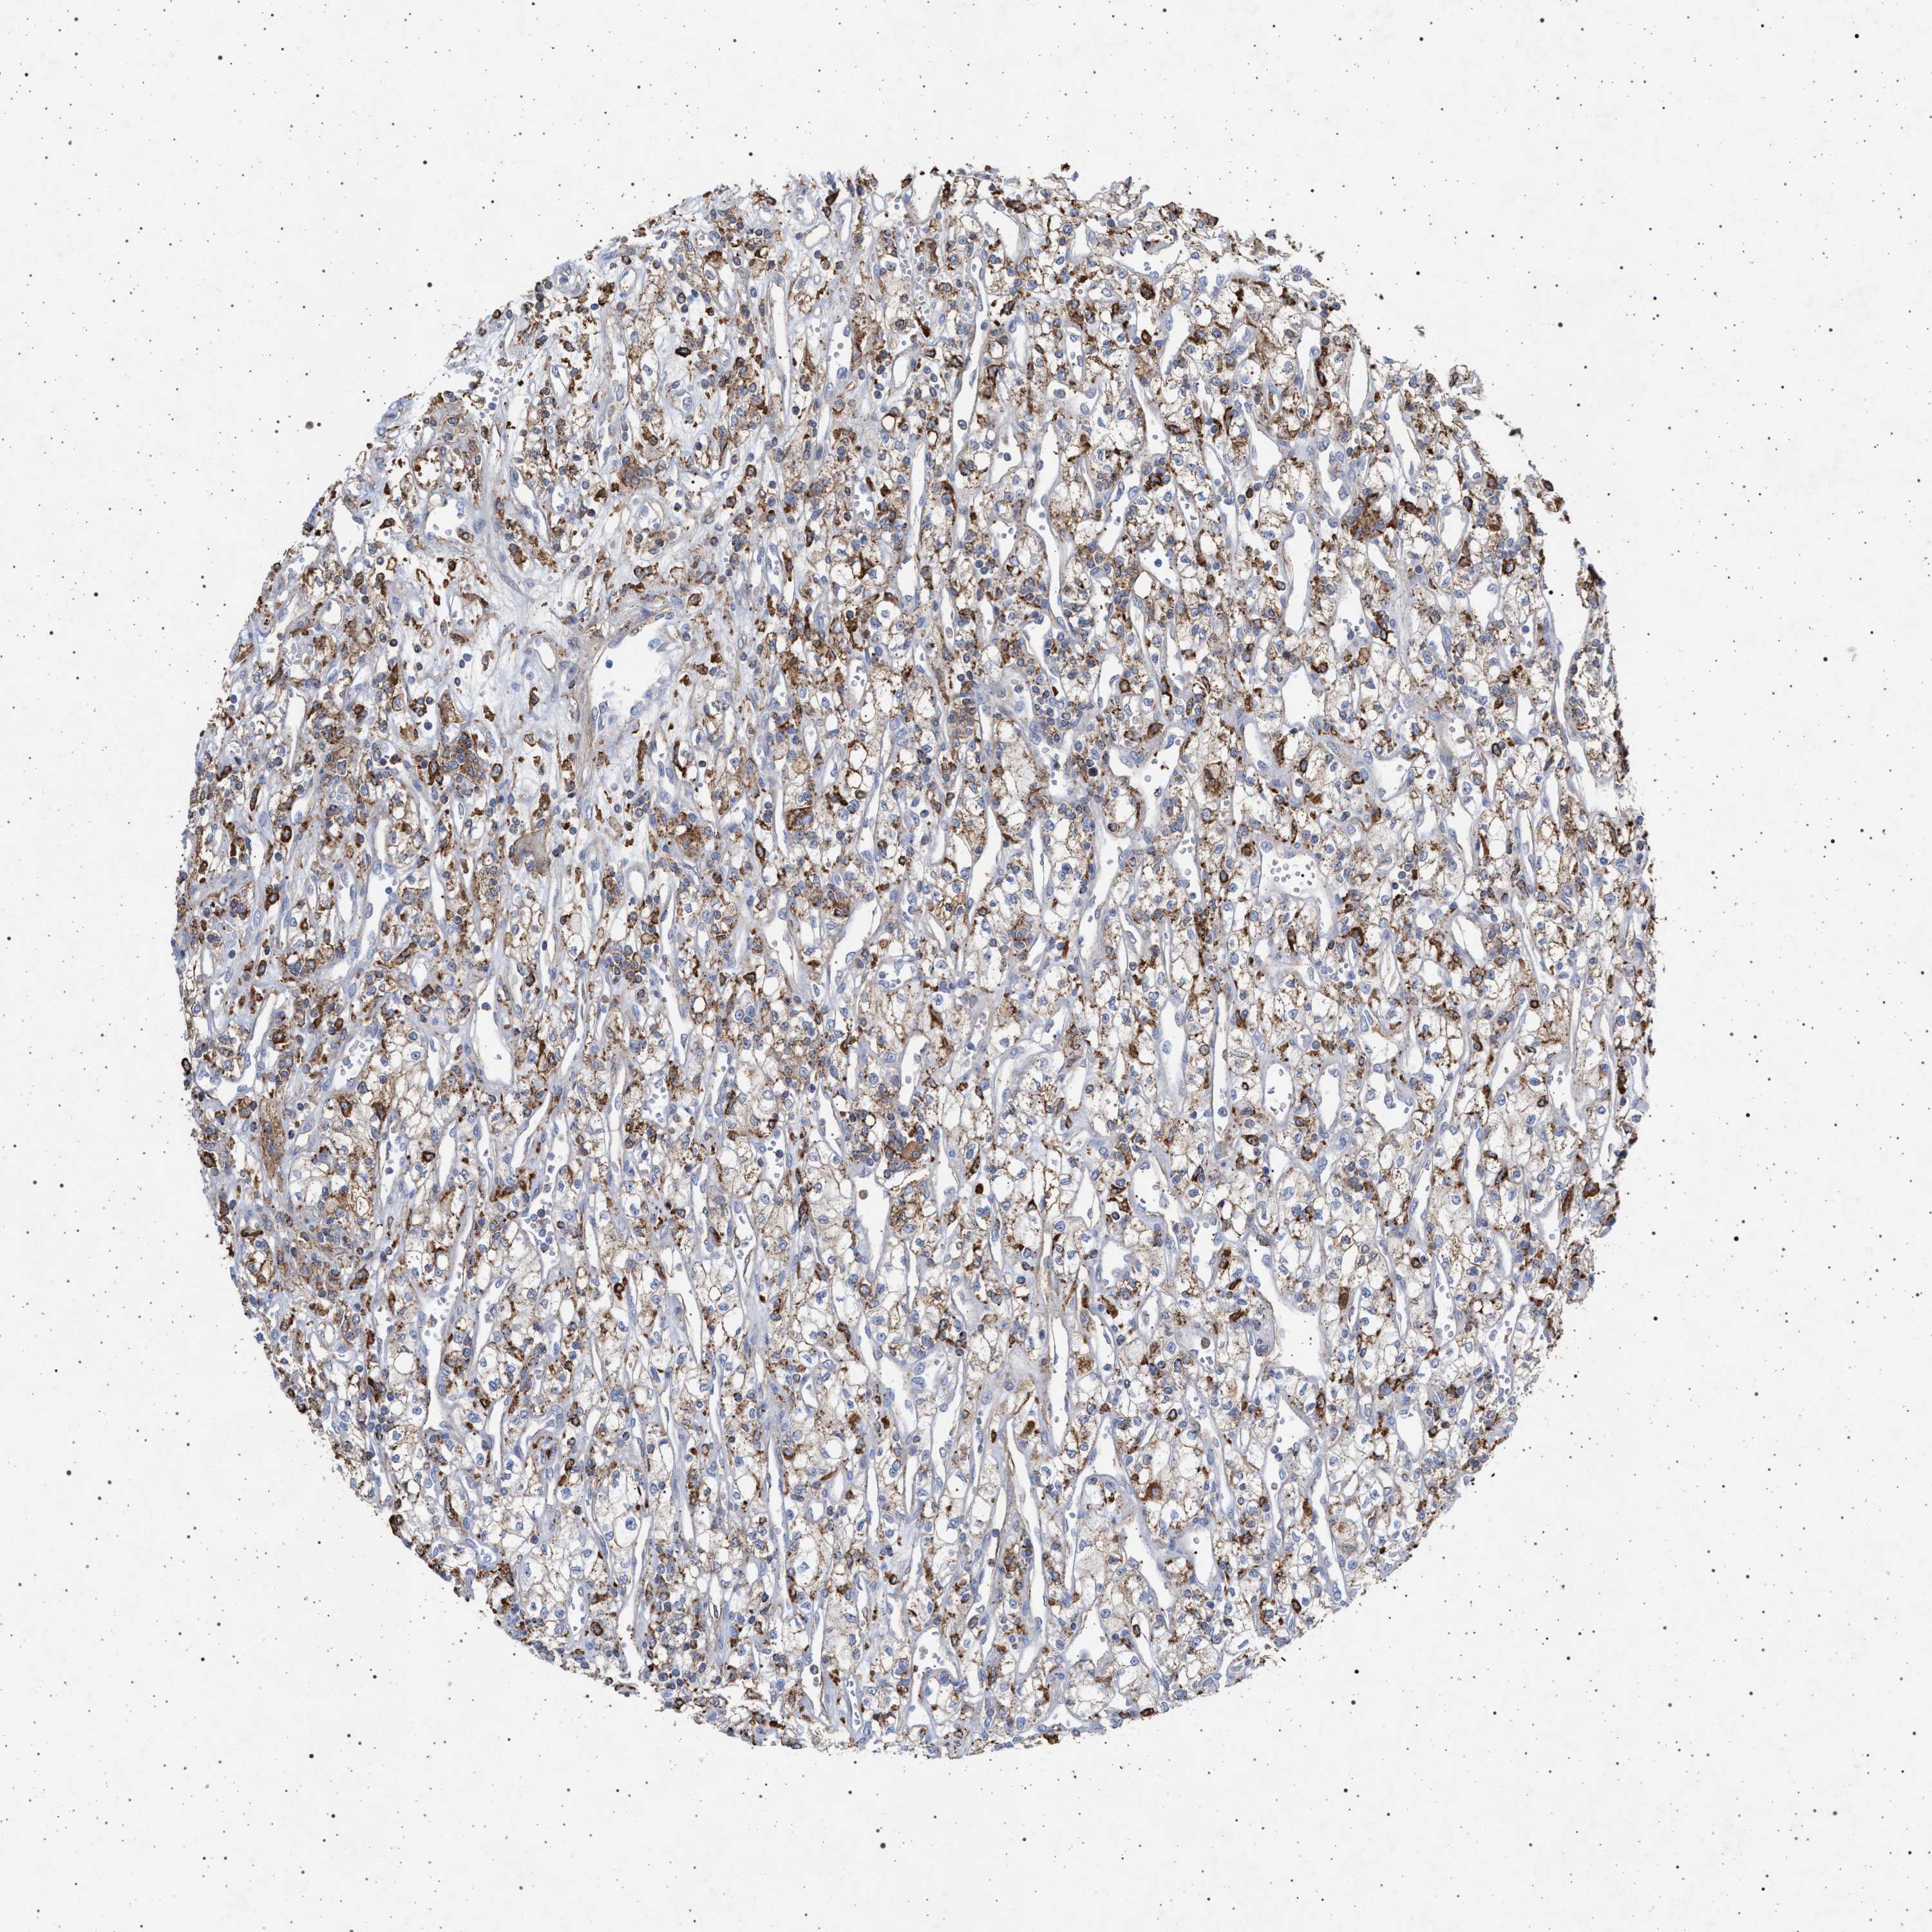

KIDNEY RENAL CLEAR CELL CARCINOMA (TCGA) - Interactive survival scatter ploti

The Survival Scatter plot shows the clinical status (i.e. dead or alive) for all individuals in the patient cohort, based on the same data that underlies the corresponding Kaplan-Meier plots. Patients that are alive at last time for follow-up are shown in blue and patients who have died during the study are shown in red.

The x-axis shows the expression levels (FPKM) of the investigated gene in the tumor tissue at the time of diagnosis. The y-axis shows the follow-up time after diagnosis (years). Both axes are complimented with kernel density curves demonstrating the data density over the axes. The top density plot shows the expression levels (FPKM) distribution among dead (red) and alive patients (blue). The right density plot shows the data density of the survived years of dead patients with high and low expression levels respectively, stratified using the cutoff indicated by the vertical dashed line through the Survival Scatter plot. This cutoff is automatically defined based on the FPKM cutoff that minimizes the p-score. The cutoff can be changed by dragging the vertical line or by entering a cutoff value in the square labeled "Current cut-off".

Under the Survival Scatter plot the p-score landscape (black curve; left axis) is shown together with dead median separation (red curve; right axis). Dead median separation is the difference in median mRNA expression between patients who have died with high and low expression, respectively. It is calculated as follows: median FPKM expression of dead patients with high expression - median FPKM expression of dead patients with low expression. This is intended to aid the user in visually exploring custom cutoffs and the associated p-scores and dead median separation.

Individual patient data is displayed and can be filtered by clicking on one or more of the category buttons on the top of the page. Categories describing expression level and patient information include: high, low, alive, dead, female, male and tumor stages. The scale of the x-axis can be toggled between linear and log-scale by clicking on the "x log" button. Mouse-over function shows TCGA ID, patient information and mRNA expression (FPKM) for each patient.

& Survival analysisi

Kaplan-Meier plots summarize results from analysis of correlation between mRNA expression level and patient survival. Patients were divided based on level of expression into one of the two groups "low" (under cut off) or "high" (over cut off). X-axis shows time for survival (years) and y-axis shows the probability of survival, where 1.0 corresponds to 100 percent.

PLG is potential prognostic, high expression is favorable in Kidney Renal Clear Cell Carcinoma (TCGA)

Best expression cut offi

Based on the FPKM value of each gene, patients were classified into two groups and association between prognosis (survival) and gene expression (FPKM) was examined. The best expression cut-off refers the FPKM value that yields maximal difference with regard to survival between the two groups at the lowest log-rank P-value. Best expression cut-off was selected based on survival analysis .

When clicking on this number, the vertical dashed line indicating cut-off, the interactive survival plot, and the Kaplan-Meier curve will be adjusted to show results based on the best expression cut-off.

: 2.09

TCGA RNA samplesi

RNA-seq data is reported as average FPKM (number Fragments Per Kilobase of exon per Million reads), generated by the The Cancer Genome Atlas (TCGA) .

Normal distribution across the dataset is visualized with box plots, shown as median and 25th and 75th percentiles. Points are displayed as outliers if they are above or below 1.5 times the interquartile range. FPKM values of the individual samples are presented next to the box plot.

Average pTPM 9.6

Number of samples 521